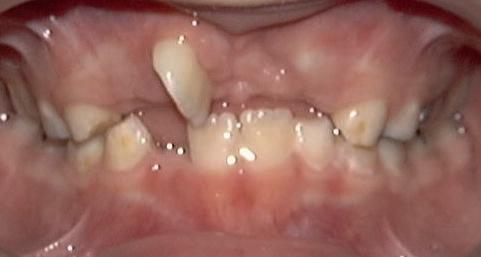

RECONFIGURAREA suportului osos implantar. În cazul prezentat, după ani de terapie ortodontică incorect executată, dezvoltarea dentară a pacientului a complicat obținerea unui zâmbet estetic. S-a reanalizat și s-a optat pentru abordare interdisciplinară care cuprinde chirurgia parodontală, un al doilea tratament

ortodontic și protetica pentru a oferi îngrijirea comprehensivă.